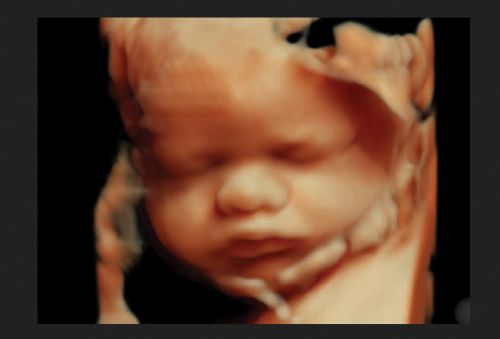

“The demise of pro-abortion Amendment 4 is a momentous victory for life in Florida and for our entire country,” said SBA Pro-Life America President Marjorie Dannenfelser. “Thanks to Gov. Ron DeSantis, when we wake up tomorrow, babies with beating hearts will still be protected in the free state of Florida.”

The defeat signals a strong conservative stance in Florida on late-term abortions and ensures that the state’s heartbeat law will continue protecting babies from abortions.